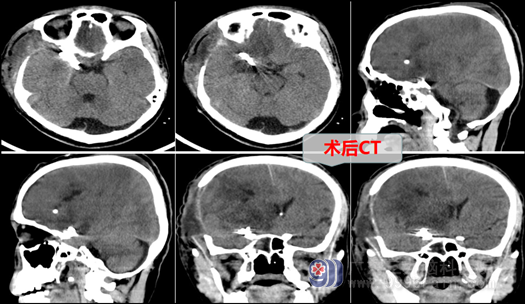

在完善相关检查后,外十科主任欧阳教授及冯桂栗医师向家属交待病情,说明手术的必要性和手术风险,如要好的治疗,必须在全麻下行右侧后交通动脉瘤夹闭术+脑室外引流术+去骨瓣减压术,由于患者动脉瘤出过血,又有多处动脉狭窄,手术过程困难,但欧阳教授等沉着、冷静,在显微镜下一丝不苟,仔细操作,终于取得圆满成功,将动脉瘤完全夹闭,并保持载瘤动脉通畅。术中仅输血200ml,术后复查CT未见脑梗塞等并发症,患者呼吸平顺,送重症监护室监护治疗。

术后第1天,患者嗜睡状,右侧肢体可遵嘱活动,术后第2天患者即可简单言语,由重症监护室转回外十科普通病房继续治疗。术后第8天,患者恢复良好,肢体活动明显好转,转康复科继续治疗,相信经过一段时间的康复,唐大哥一定可以恢复到和以前一样健康。